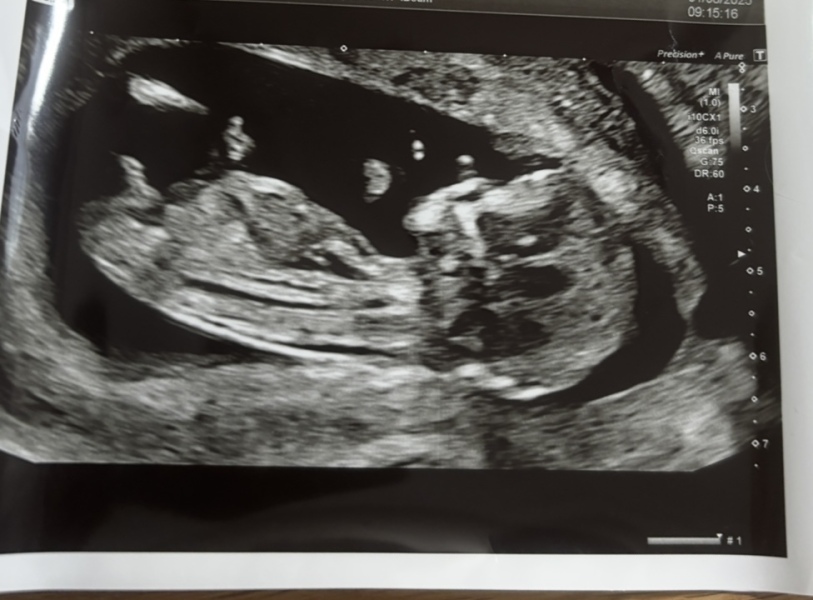

Everyone has said 100% clear boy but I’m just not convinced, what does everyone reckon? Is this a boy nub or something else. Just seems rather large and too clear. Was taken at 13w. I’ve attached all the scan pics x

Unless you might think your baby has a tail, that’s a boy.

you can see both legs and they look nothing like the nub.

That made me laugh 🤭 I’ve been down an absolute rabbit hole of the nub theory and I think the only reason I’m not convinced is I’m yet to see another that’s so prominent and clear 🤣 let’s hope he doesn’t have a tail